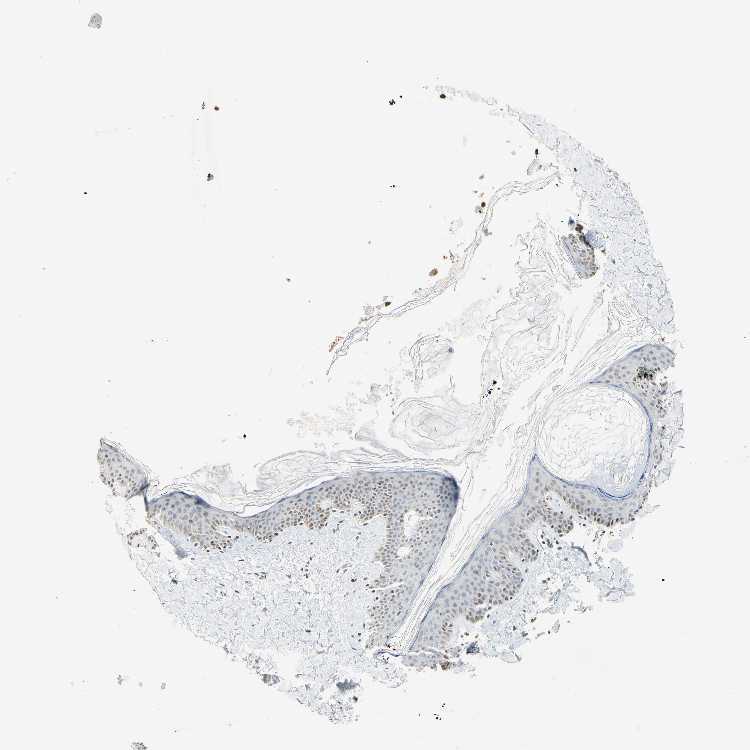

TISSUE PRIMARY DATA SKIN Show tissue menu

SKIN 1 - Antibody stainingi

Antibody staining in the annotated cell types in the current human tissue is reported as not detected, low, medium, or high, based on conventional immunohistochemistry profiling in selected tissues. This score is based on the combination of the staining intensity and fraction of stained cells.

Each image is clickable and will lead to virtual microscopy that enables deeper exploration of all samples and also displays staining intensity scores, fraction scores and subcellular localization as well as patient and tissue information for each sample.

SKIN 2 - Antibody stainingi